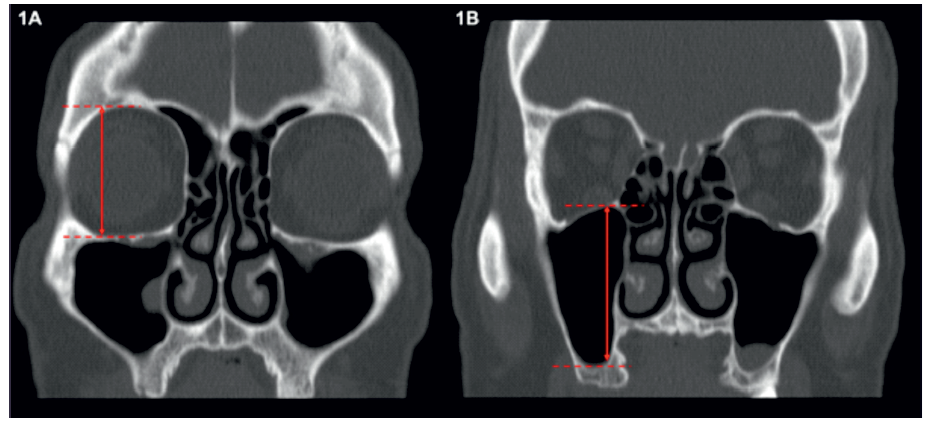

Em todos os lados analisados foi avaliado o grau de pneumatização do seio maxilar utilizando os critérios descritos por Soyal e colegas (6). Para tal, inicialmente foram medidos os diâmetros máximos (vertical e transversal) de cada órbita e de cada seio maxilar (Figura 1). Seguidamente, para cada lado, foi calculada a razão entre o diâmetro máximo do seio maxilar e o diâmetro máximo da órbita ipsilateral (diâmetro máximo do seio maxilar/ diâmetro máximo da órbita). Nos casos em que o resultado era <0,5 o seio era classificado como hipoplásico, se fosse ≥ 0,5 e ≤ 1 era normal e se fosse > 1 era classificado como hiperplásico.

Figura 1 Demonstração da medição dos diâmetros verticais máximos da órbita direita (A) e do seio maxilar direito (B) para avaliação do grau de pneumatização do seio maxilar direito.